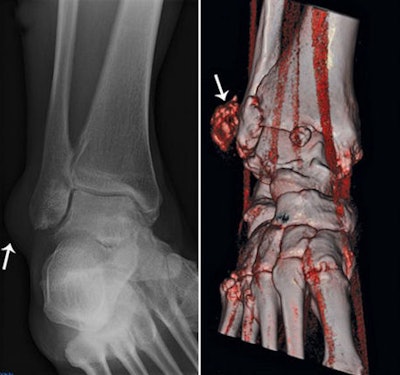

![]() |

| syngo dual-energy CT software, Siemens Healthcare. The algorithm driving the syngo graphical user interface (above) plots uric acid versus calcium. The y-axis represents the attenuation values of the lower kilovoltage tube (80 kV), and the x-axis represents the attenuation values of the higher kilovoltage tube (140 kV). Pixels with a higher slope (high atomic number) are plotted above the line and represent calcium; the pixels below the line represent uric acid (lower atomic numbers of its component elements). Maximum and minimum values can be defined for soft tissue to improve performance of the algorithm. The algorithm ignores CT values outside this range. All images © 2010 American Roentgen Ray Society. |